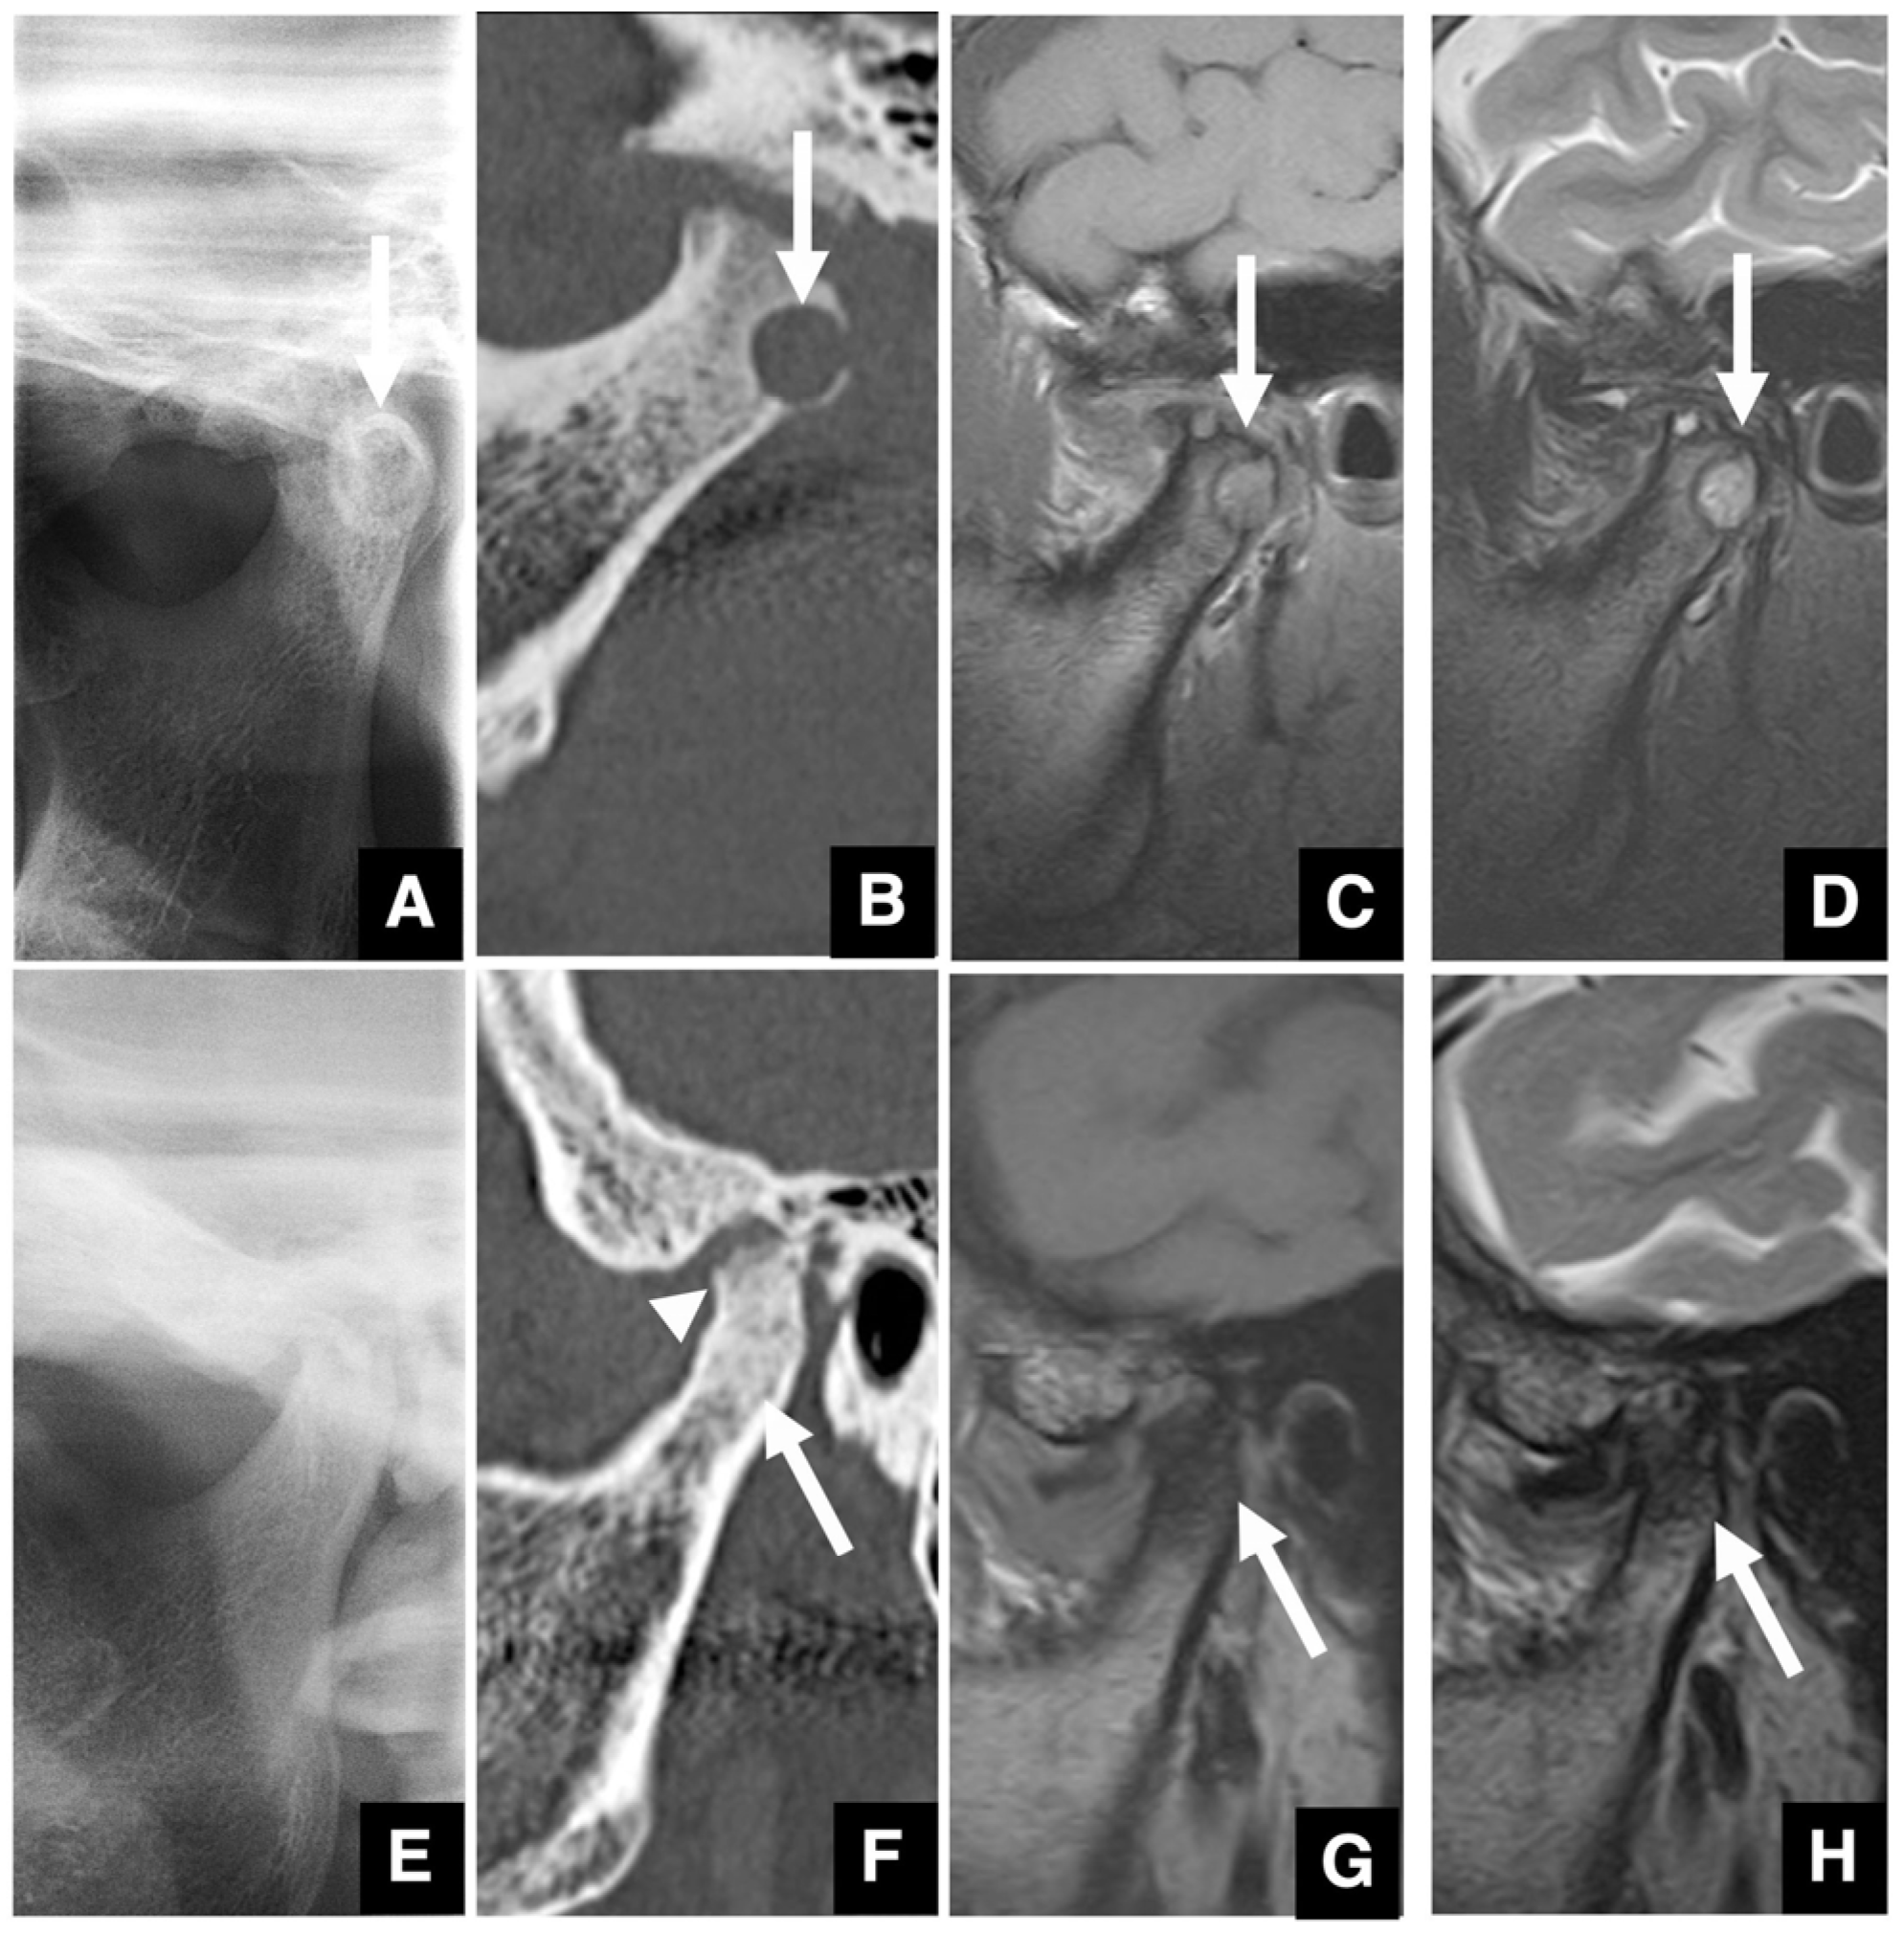

| Setting the osteotomy line 1. Evaluation of the position of the mandibular canal and surrounding bone quality Presence or absence of mandibular canal bifurcation and course of resection site Distance from the buccal wall of the mandibular canal to the buccal cortical bone margin Bone quality around the mandibular canal (CT number) 2. Distance from the mandibular notch to the lingula Whether it is 14 mm or more 3. Morphology of the mandible and variation in cortical bone thickness Cortical bone thickness in the medial osteotomy area and lateral osteotomy area Enhanced safety through improved visibility 1. Medial curvature of the mandibular ramus Mandibular ramus is straight or strong curvature 2. Course of small blood vessels along the bone surface Depression of the buccal-lingual cortical bone from the mandibular fossa to the mandibular ramus region, trabecular bone defect Improved success rates through enhanced postoperative bone integration 1. Degree of interference between bone segments The presence or absence of interference between the proximal and distal bone segments formed during virtual mandibular deformity surgery |

| Improving safety through prediction of surgical difficulty and complication 1. Circumstance of pterygoid venous plexus Carefully observe the fat tissue surrounding the medial and lateral pterygoid muscles to assess the development of the internal vascular structures (using CT and MR to evaluate the size of the fat tissue) 2. Fusion status of the maxillary tuberosity and pterygomaxillary suture When the fusion is narrow and the degree of calcification (CT number) is low or when the fusion is wide and high 3. Course of the descending palatine artery and thickness of surrounding bone When the palatal canal wall is thick, the probability of damage during transection is low. When it is thin, the possibility of damage cannot be ruled out. Setting the osteotomy line 1. Distance from the piriform rim to the greater palatine canal Long, short, cortical bone thickness, presence or absence of bone irregularities 2. Evaluation of the size, morphology, and internal features (mucosa, septa, etc.) of the maxillary sinus Size, shape, presence or absence of septa, presence or absence of masses, presence or absence of mucosal thickening 3. Relationship between the floor of the maxillary sinus and the apices of the molars Describe the maxillary sinus floor and the apex of each molar tooth 4. Presence of nasal septal deviation, size of the nasal passages, and thickness of the lateral nasal wall bone Presence or absence of nasal septal deviation, Size of the nasal passage, Thickness of the cortical bone of the lateral wall 5. Course of the mandibular artery The course from the pterygoid cleft to the pterygopalatine fossa in the posterior maxilla |

- Hwang, K.; Nam, Y.S.; Han, S.H. Vulnerable structures during intraoral sagittal split ramus osteotomy. J. Craniofac. Surg. 2009, 20, 229–232. [Google Scholar] [CrossRef]

- Jo, H.W.; Kim, Y.S.; Kang, D.H.; Lee, S.H.; Kwon, T.G. Pseudoaneurysm of the facial artery occurred after mandibular sagittal split ramus osteotomy. J. Oral Maxillofac. Surg. 2013, 17, 151–154. [Google Scholar] [CrossRef] [PubMed]

- Tsurushima, H.; Yoshioka, I. Imaging diagnosis for safe mandibular orthodontic surgery. Jpn. J. Oral Diag. 2023, 36, 99–105. (In Japanese) [Google Scholar] [CrossRef]

- Kuroyanagi, N.; Miyachi, H.; Kanazawa, T.; Kamiya, N.; Nagao, T.; Shimozato, K. Morphologic features of the mandibular ramus associated with increased surgical time and blood loss in sagittal split-ramus osteotomy. J. Oral Maxillofac. Surg. 2013, 7, e31–e41. [Google Scholar] [CrossRef]